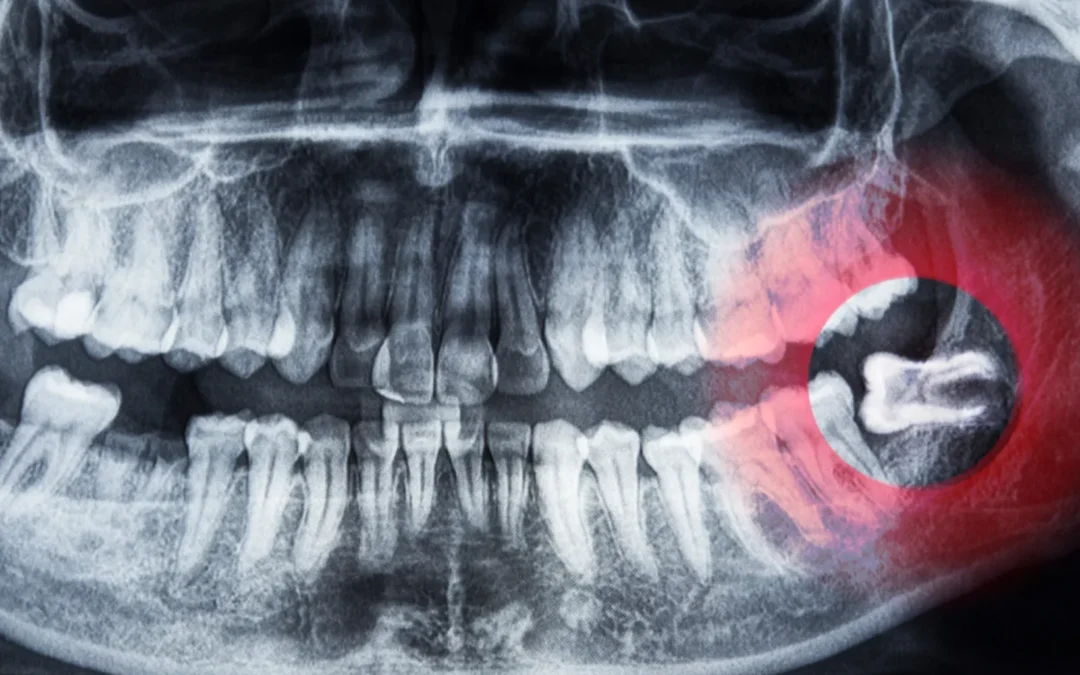

Ząb mądrości

Ząb mądrości — kiedy lepiej się z nim pożegnać? Usunięcie tzw. „ósemek” to częsty i w wielu przypadkach konieczny zabieg, który pozwala uniknąć wielu powikłań w przyszłości. Dlaczego warto go rozważyć i jak wygląda cały proces?Zęby mądrości usuwa się ponieważ: Często...